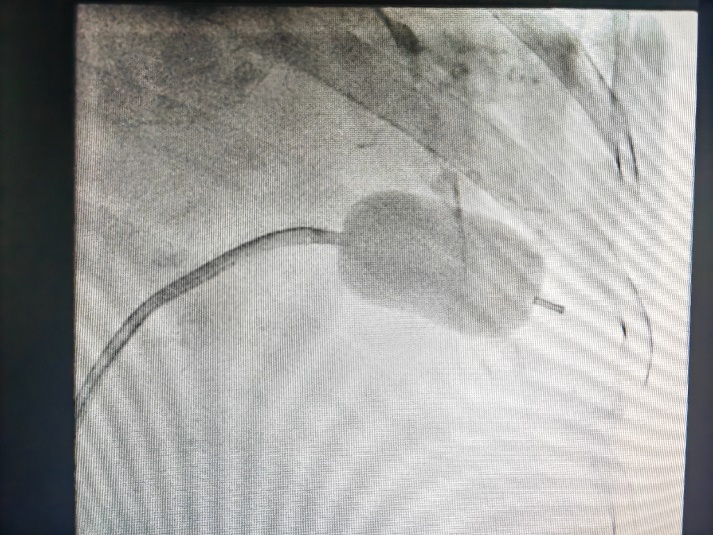

此例手术由姚晓伟主任医师、韩稳琦主治医师、赵永勇主治医师通过心腔内超声指导下进行,通过心腔内超声精准构建心脏模型、直视下穿刺房间隔,后通过心腔内超声及左心房造影寻找狭窄的二尖瓣瓣口,并指引二尖瓣球囊扩张导管顺利经狭窄的二尖瓣口至左心室,在心腔内超声的指引下选择最佳位置以26mm球囊导管反复扩张狭窄的二尖瓣。术后第二天复查心脏超声,患者二尖瓣瓣口面积由术前0.67cm2扩大到术后1.69cm2,二尖瓣跨瓣压差由术前22mmHg降低至术后的16mmHg,左房前后径由术前94mm减小至术后92mm,左房左右径由术前109mm减小至术后102mm,并且球囊扩张后未引起明显的二尖瓣反流,患者心功能明显改善,自觉症状明显好转出院。

图四:球囊对狭窄的二尖瓣进行扩张